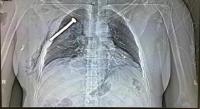

متفرّقات

23 مارس 2016 (14:07)

صور بالأشعة إكس تكشف إستعمال قنابل مسمارية في تفجيرات بروكسل